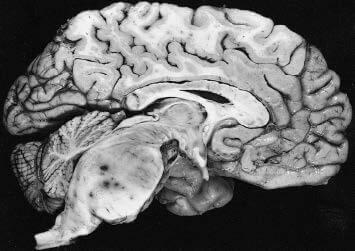

Brain Tumour Types

• Brain Tumour Types